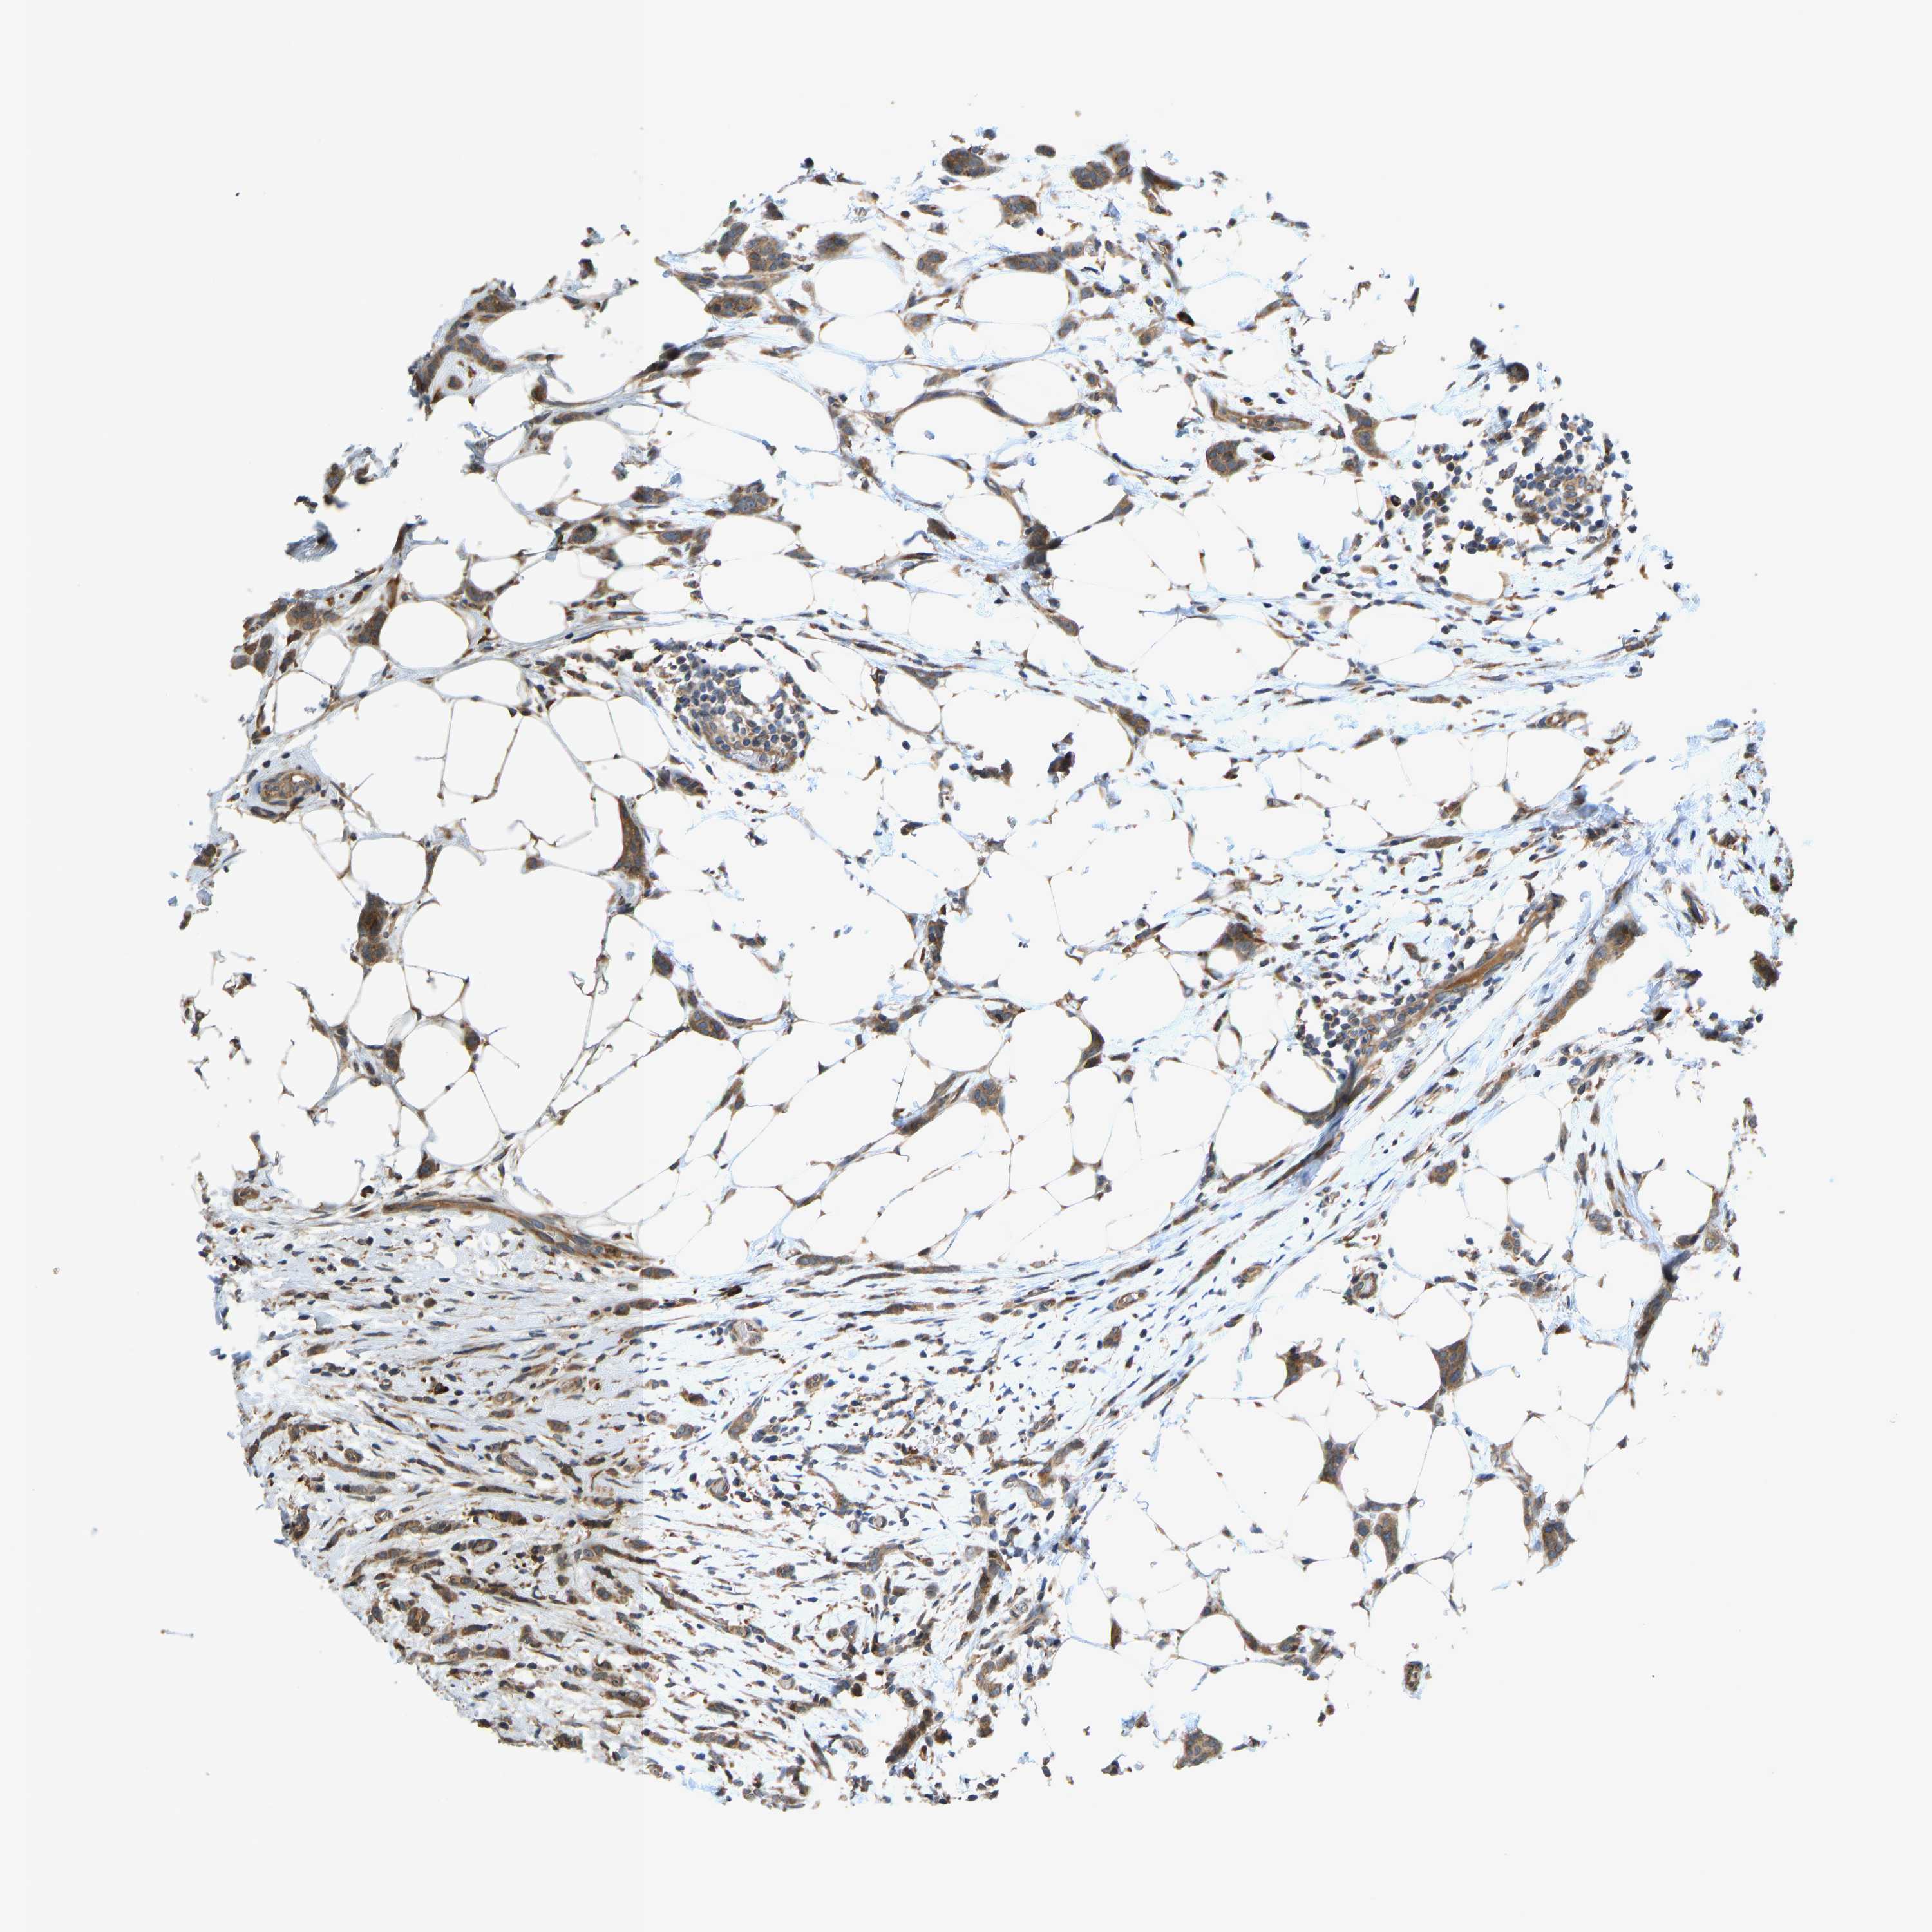

CANCER BREAST CANCER Show tissue menu

BRCA TCGA BRCA VALIDATION PROTEIN EXPRESSION

ANTIBODIES

AND

VALIDATION